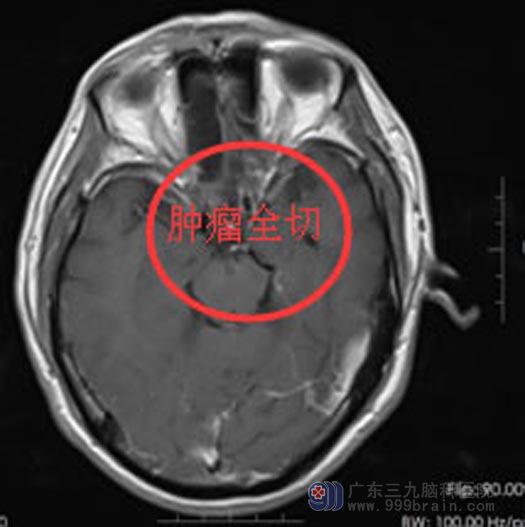

明确诊断后,由鲁明副院长主刀行“经前纵裂颞底入路鞍结界脑膜瘤切除术”。术中可见肿瘤两侧临近视神经与颈内动脉,显微镜下细致分块、完整切除肿瘤,垂体柄与重要的血管保护完好。

手术后吴叔的左眼视力及头痛症状都有了明显的好转。

手术后